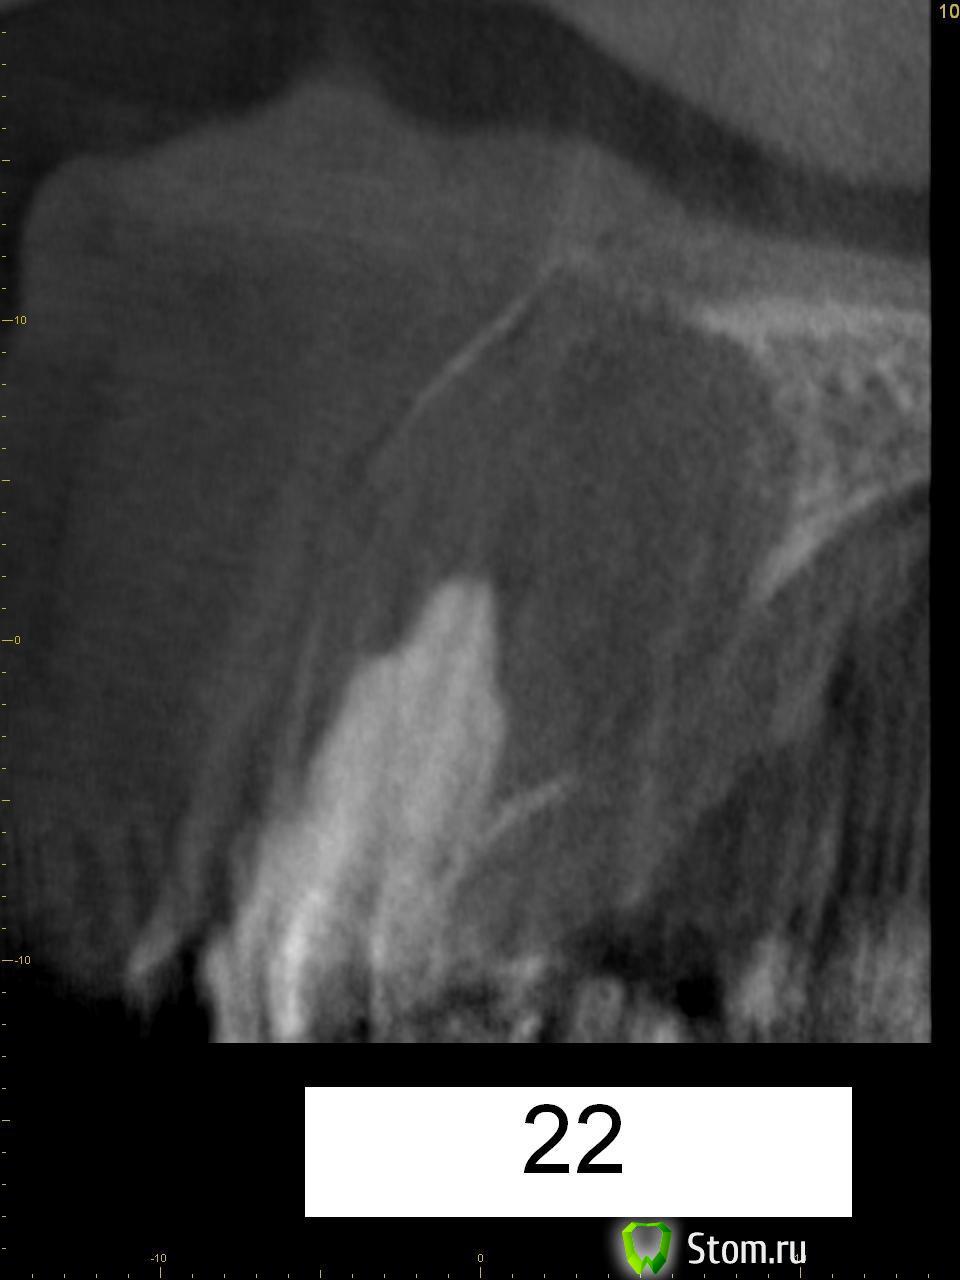

wladdX Опубликовано 22 января, 2014 Поделиться Опубликовано 22 января, 2014 (изменено) Пациентка 33-х лет, обратилась с жалобами на болезненную припухлость на тв. нёбе. При обследовании выявлена киста резцового канала, самопроизвольно вскрывшаяся.Через перф.отверстие отмыта, воспаление стихло, свищевого хода не сформировалось (перф.отверстие эпителизировалось). Встаёт вопрос об операции. Планируется нёбный доступ. Как думаете, коллеги? Изменено 22 января, 2014 пользователем wladdX Ссылка на комментарий

kriokov Опубликовано 28 января, 2014 Поделиться Опубликовано 28 января, 2014 В моем случае имплантация не планировалась в перспективе, поэтому без графта и мембраны, с удалением 21 и 22, штатная цистэктомия вестибулярным доступом.В Вашем случае сделал бы с неба, (чего полсантиметра окно делать , если с вестибулярного доступа идти) , без графта и мембраны, там размеры костного дефекта маленькие , около 1 см, и дефект почти замкнутый будет, он хорошо и без графта восстанавливается.. Чувствительность может пропасть на небе макс на полгода, пациентов потеря ее в этой области мало тревожит. Ссылка на комментарий

wladdX Опубликовано 29 января, 2014 Поделиться Опубликовано 29 января, 2014 Так и предполагаю. Тем более зубы 11 и 21 витальные. Ссылка на комментарий